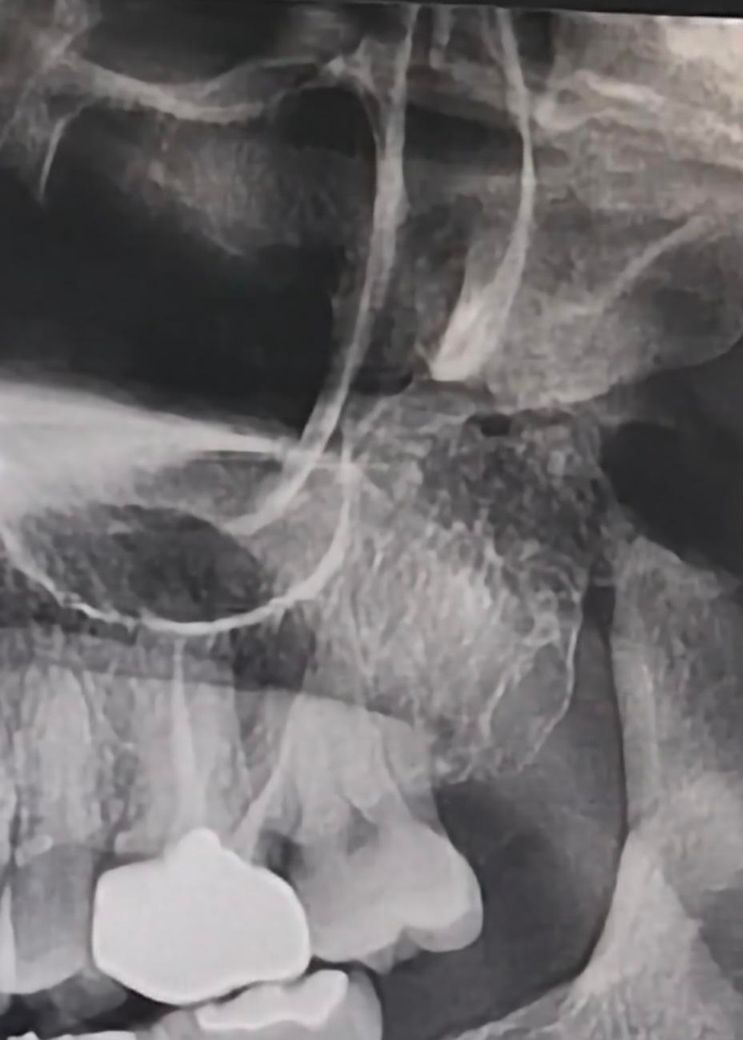

금니크라운인데 혹시 금니에 틈이 있나요?

엑스레이 상의 오류일수도 있고, 크라운 아래쪽으로 충치가 생겨서 그럴가능성도 있습니다.

엑스레이 사진상으론 크라운 하방으로 틈이 있어서 이차충치가 생기고 있는 것으로 보입니다 잇몸 염증 증상도 있으니 치과가서 한번 검사해보세요